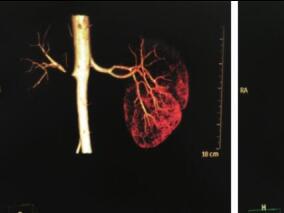

1小时条评论33岁年轻女性,发现血压升高4年,联用两种降压药物,血压控制欠佳,无肥胖史、夜间打鼾史、高血压家族史,肾动脉CT示肾动脉中远段狭窄,呈不典型的串珠样改变,因此诊断考虑肾动脉纤维肌性结构发育不良。 病史摘要 患者女性,33岁,主因血压升高4年入院。患者4年前...